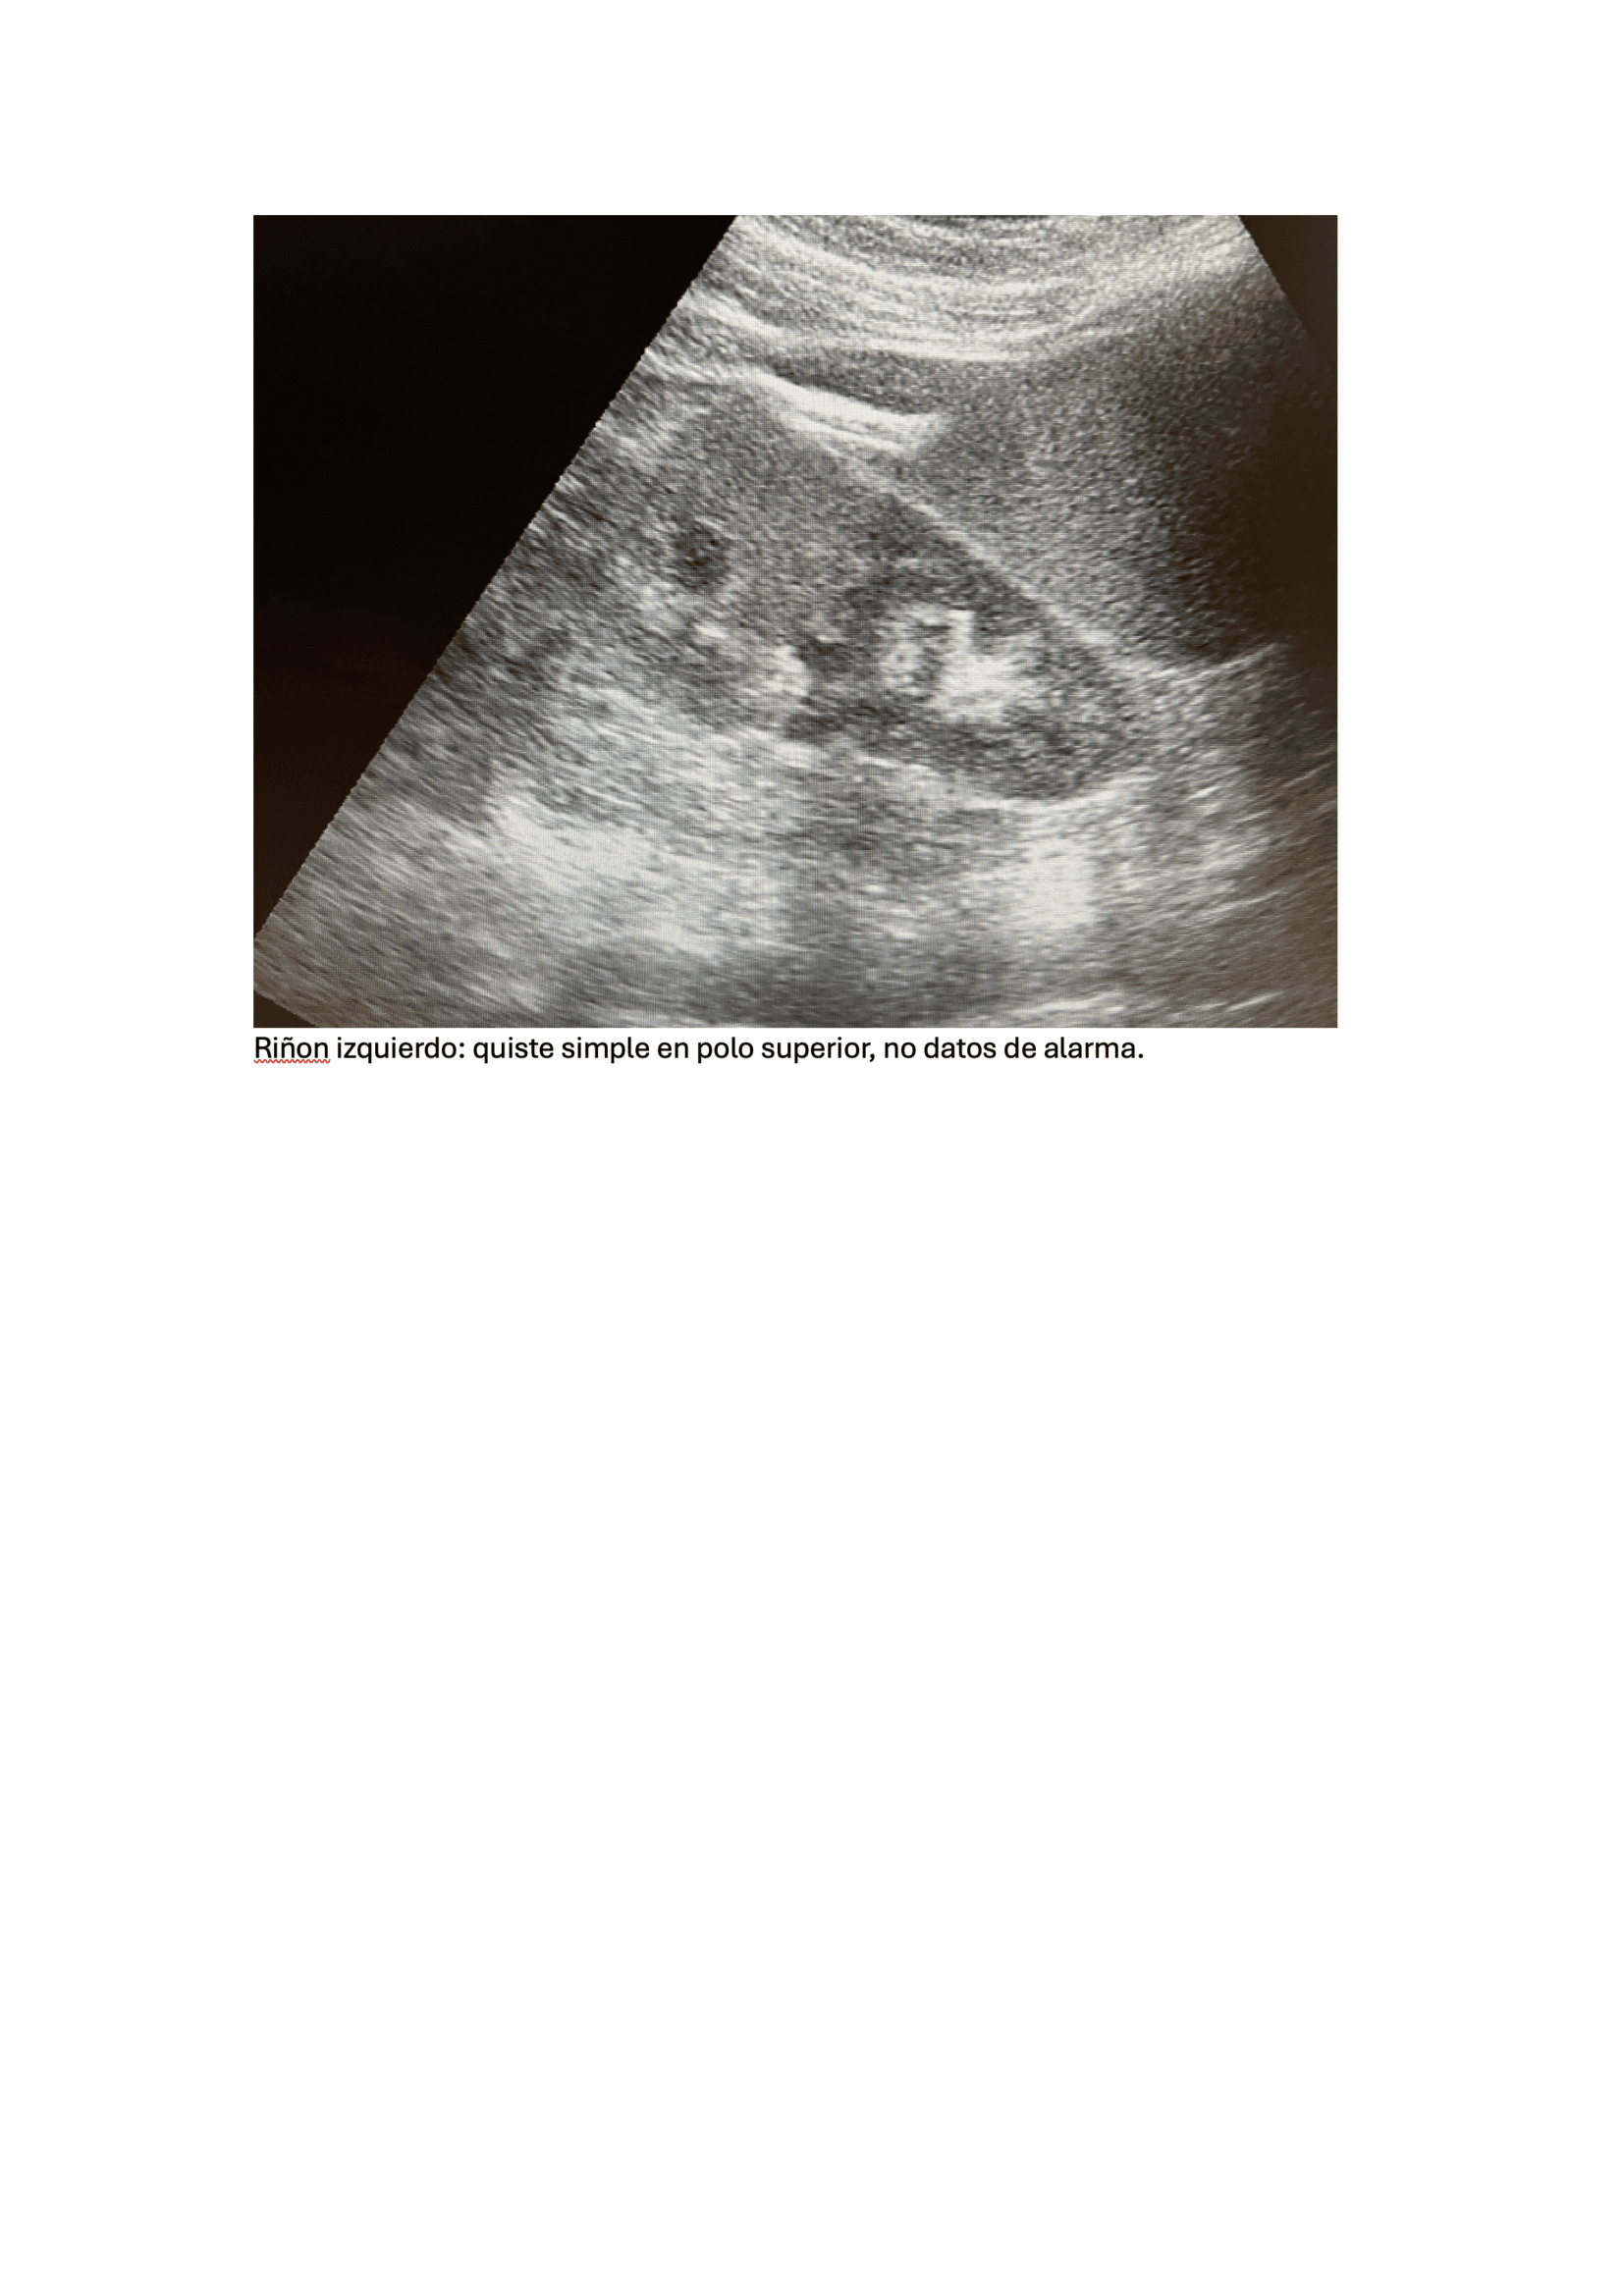

Urología: evidencia mejoría del cuadro clínico, niega fiebre, dolor. Refiere expulsión de pequeño cálculo tras 5 días de tratamiento. Ecografía, Riñón de tamaño normal, homogéneo, se evidencia imagen litiásica que deja sombra acústica posterior de 1,2 cm x 9 mm aprox. que no compromete vía urinaria, no dilatación de pelvis renal. Se deja tratamiento con tamsulosina durante 3 meses hasta nueva valoración. Control con su médico de familia, solicitar seguimiento de niveles ácido úrico y si alteración pautar tratamiento.